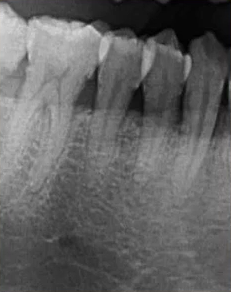

临床检查45叩诊(+),牙颌面见畸形中央尖。加拍根尖片可看到,右下5根方有低密度影,并且右下5的牙根较短小,和曲面断层片上显示的大小不同,所以右下5是舌向倾斜的牙齿。

曲面断层片怎么看口腔精读 | 一次性教你看懂曲面断层片!_https://www.jmylbn.com_新闻资讯_第25张

曲面断层片怎么看口腔精读 | 一次性教你看懂曲面断层片!_https://www.jmylbn.com_新闻资讯_第26张